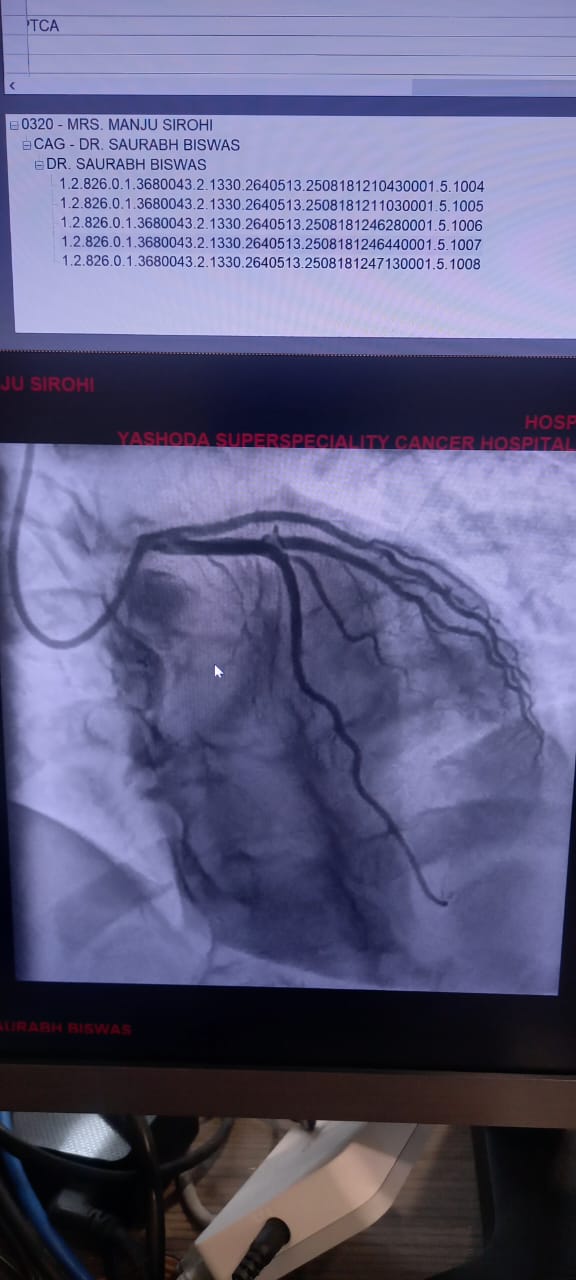

Angiography / Cardiac Cath

Angiography, also known as Cardiac Catheterization, is a minimally invasive procedure used to diagnose heart conditions. It provides detailed images of the heart's blood vessels, helping doctors detect blockages or narrowing.

Once it reaches the heart, a contrast dye is injected. The dye makes the coronary arteries visible on an X-ray screen, revealing any blockages, plaque buildup, or structural issues.

• Coronary Angiography: This is the most common type. It evaluates the coronary arteries for blockages or narrowing.